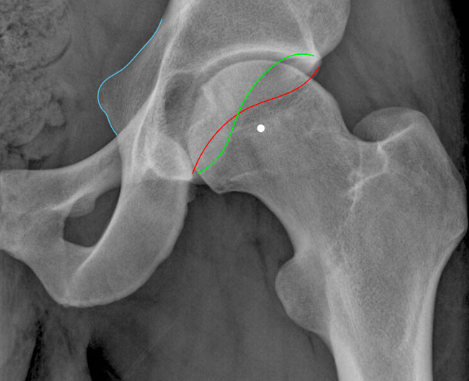

• Crossover sign - anterior wall extends lateral to the posterior wall

• Ischial spine sign - ischial spine projects more medially than normal into the pelvis

Normal hip - anterior acetabular wall (red line) is medial to the posterior acetabular wall (green line). Also note the ischial spine (blue line) isn’t overly projected into the pelvis